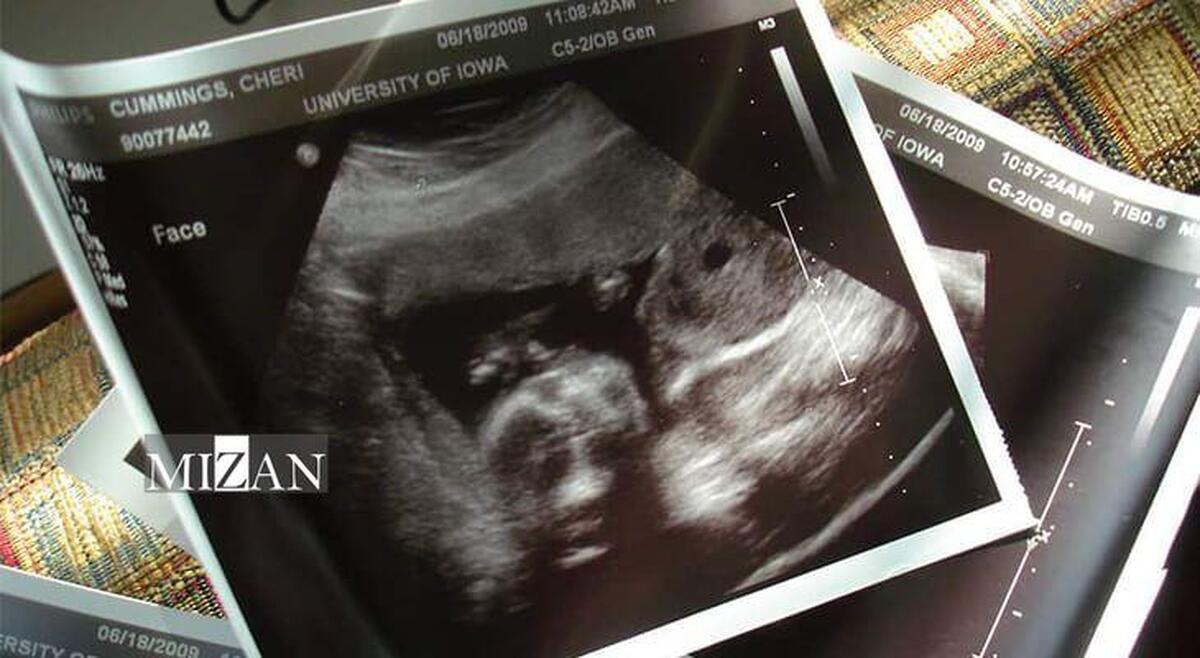

سامانه ۴۰۳۰ در خدمت پیشگیری از سقط جنین/ آموزش تخصصی به ۳۰۰ مشاور تلفنی

به گزارش مرکز ارتباطات و اطلاعرسانی ستاد اجرایی فرمان امام، امیرحسین مدنی با اشاره به استفاده از ظرفیت سامانه تلفنی ۴۰۳۰ در این طرح، گفت: فعالیت سامانه ۴۰۳۰ در حوزه جوانی جمعیت با حضور ۱۵ مشاور در بخش پیشگیری از سقط جنین آغاز شده است و پس از برگزاری این دوره آموزشی در مرحله نخست بیش از ۳۰۰ نفر به مشاوران این سامانه اضافه خواهد شد.

مدیرعامل بنیاد برکت ستاد اجرایی فرمان امام با بیان اینکه افراد نیازمند به مشاوره در موضوع پیشگیری از سقط جنین در سراسر کشور میتوانند از طریق سامانه تلفنی ۴۰۳۰، خدمات مشاوره را به طور رایگان در این زمینه دریافت کنند، افزود: با توجه به تجربه موفق سامانه ۴۰۳۰ در ایام کرونا، این سامانه در رویکرد جدید خود با ایجاد شرایطی امن، محرمانه، تخصصی و با حفظ شأن مخاطب، خدمات مشاوره تلفنی را در حوزه پیشگیری از سقط جنین به طور موثرتر ارائه میکند.

وی خاطر نشان کرد: در آیندهای نزدیک، دیگر موضوعات حمایتی نیز به این سامانه مشاوره تلفنی اضافه خواهد شد به صورتی که اگر افرادی به علت مسائل مالی و مشکلات معیشتی بخواهند اقدام به سقط جنین کنند، از طریق این سامانه به بنیاد برکت معرفی خواهند شد تا به این افراد کمکهای لازم در اسرع وقت صورت پذیرد.